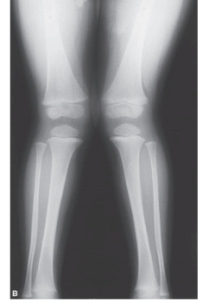

10

-Refer to the figure. The developmental deformity shown here is described as:

A) Bilateral genu varum

B) Bilateral genu valgus

C) Ipsilateral genu valgus

D) Contralateral genu varum